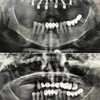

Implant tedavisi

Laminate veneer